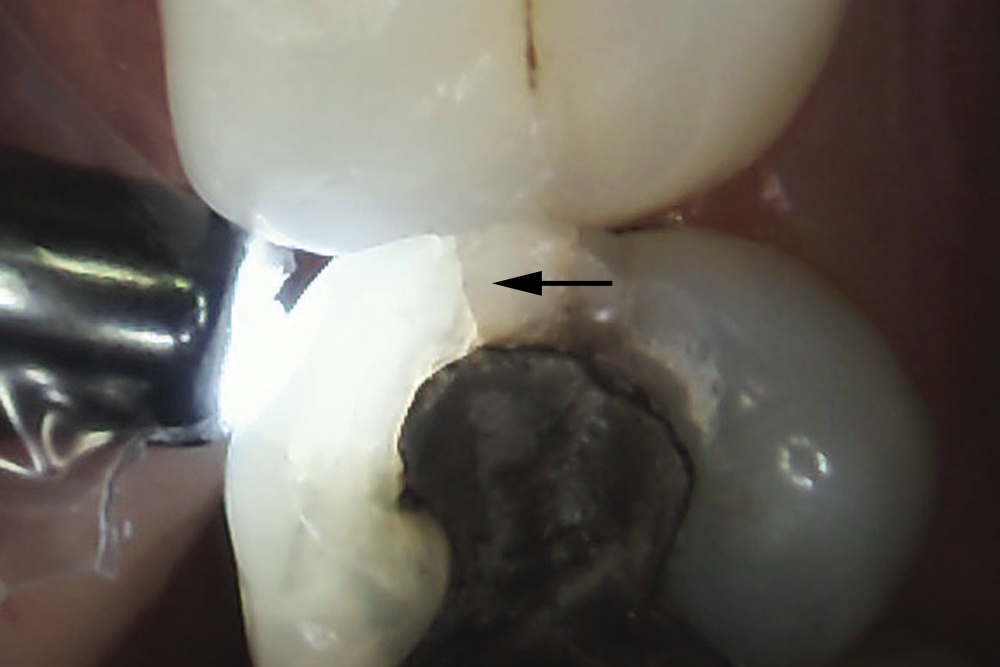

Fig 1. Decalcification in enamel along a crack line (arrow) and caries at the dentin-enamel junction of a mandibular left first molar (disto-occlusal view).

Figure 1

The detrimental effects of vertical cracks on the dentition and surrounding tissues stem mostly from bacterial invasion into the microscopic space of the crack, as well as physical irritation and liquid microleakage, even though the separation of the segments may not be clinically visible.3,5-7 As bacteria penetrate cracks, they invade underlying structures, such as the coronal dentin, pulp, root structure, and periodontal tissues, leading to varying degrees of pathologies. Enamel cracks have been found to provide caries-producing bacteria access to the dentin-enamel junction, leading to caries inside the tooth without any externally visible evidence (Figure 1).5 Dentin cracks are pathways of bacteria to the dentinal tubules and pulp, leading to various pulpal pathologies, including reversible and irreversible pulpitis and pulp necrosis.6,8